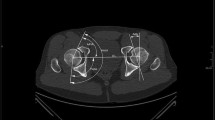

All MRI examinations were evaluated for the presence of an osseous defect in the anteroinferior aspect of the femoral head, termed femoral head defect (FHD). All 970 MRI examinations were independently assessed by two fellowship-trained musculoskeletal radiologists for the presence and location of FHD and categorized its morphology. Both radiologists were blinded for review. The location of the FHD was determined in a sagittal plane using a schematic clock face, 9:00 being the anterior position on a hypothetical horizontal line through the middle of the femoral head, 3:00 posterior position, 12:00 defined as the superior position on a vertical line through the center of the femoral head, and 6:00 as the inferior position the same line (Fig. 1). Only defects in the anteroinferior quadrant of the femoral head were recorded as FHD. Lesions in the anterosuperior, superior, and posterosuperior location of the femoral head were counted as herniation pits.

The most frequent morphology of FHD was type I (34/68; 50%), followed by type II (27/68; 40%) and III (7/68; 10%). The mean distance of FHD to the scar of the physis was 9.9 mm ± 3.7 (min. 2.3 mm, max. 18 mm) measured on a coronal plane confirming that the FHD is not a physeal remnant. On a clockface of the femoral head on a sagittal plane, the defect was most often located at the 8 o’clock position (± 0.4, range from 6:30 to 8:30) (Fig. 6).

a Schematic drawing of the medial view of the femoral head and proximal femur indicating the spatial orientation and schematic clockface used to localize the FHD in the anteroinferior quadrant. b Boxplot showing the distribution of FHD according to location on the schematic clockface between the 6:30 and 8:30 position. Solid box includes first to third quartile; the dark line at the top of the box is the median (the overwhelming majority of FHD were located at the 8 o’clock position). Whisker indicates 95% confidence interval, and dots indicate outliers